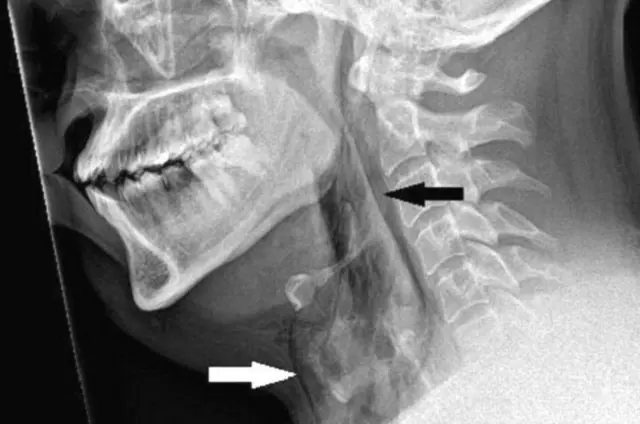

Kwa kuzuia chafya hiyo, koo lake lilikuwa na upana wa milimita 2. Ilibainika kupitia uchunguzi na kuonekana jera alilokuwa nalo.

Chanzo cha picha, BMJ

Katika uchunguzi wa mtu aliyepata majeraha, madaktari wanasema sauti ilikuwa ikitoka kooni na mtu huyo alishindwa kuizuia. Wakati wa kupiga chafya, mtu huyo alikuwa akiendesha gari akiwa amejifunga mkanda kwa mujibu wa madaktari.